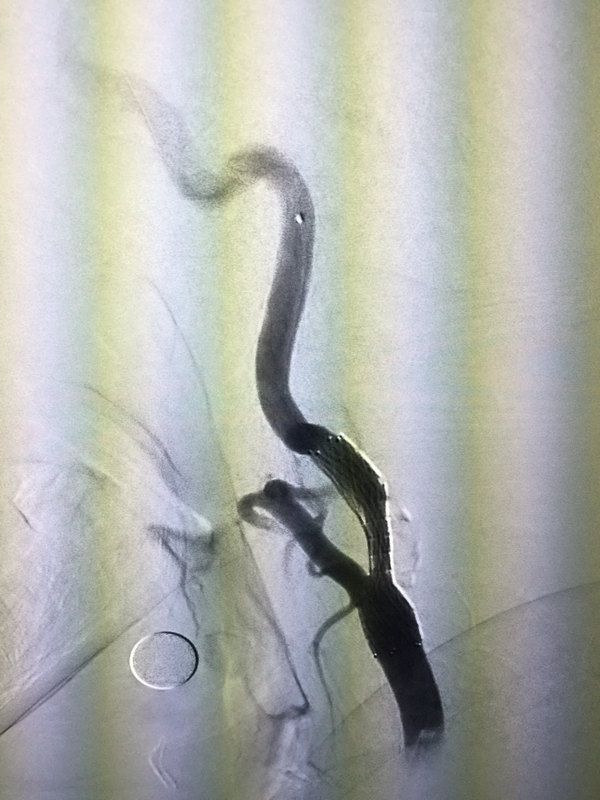

七月前左椎動脈支架3.5x13mm,術(shù)后七月再狹窄,原支架位置偏低。微導(dǎo)絲幸運(yùn)通過原支架,球囊通過困難調(diào)整后通過3.0x15mm球囊擴(kuò)張,guiding推入原支架中部,通過3.5x13mm阿波羅支架,擴(kuò)張釋放后血流良好,一例成功的再狹窄處再次支架植入病例。